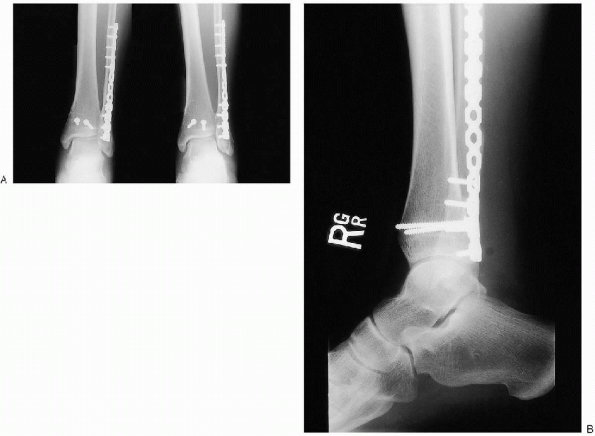

![]()  |

FIGURE 33-27. Final intraoperative anteroposterior (A), mortise (B), and lateral (C) radiographs.

range of motion to assess fixation stability. Intraoperative

adequate (Fig. 33-27). I obtain anteroposterior, mortise, and lateral views.